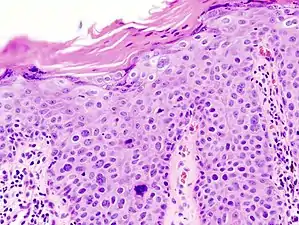

Squamous-cell carcinoma in situ, showing prominent dyskeratosis and aberrant mitoses at all levels of the epidermis, along with marked parakeratosis.[12]

Bowen's disease is essentially equivalent to and used interchangeably with cSCC in situ, when not having invaded through the basement membrane.[12] Depending on source, it is classified as precancerous[13] or cSCC in situ (technically cancerous but non-invasive).[47][48] In cSCC in situ (Bowen's disease), atypical squamous cells proliferate through the whole thickness of the epidermis.[12] The entire tumor is confined to the epidermis and does not invade into the dermis.[12] The cells are often highly atypical under the microscope, and may in fact look more unusual than the cells of some invasive squamous-cell carcinomas.[12]

cSCC in situ, high magnification, demonstrating an intact basement membrane.[12]